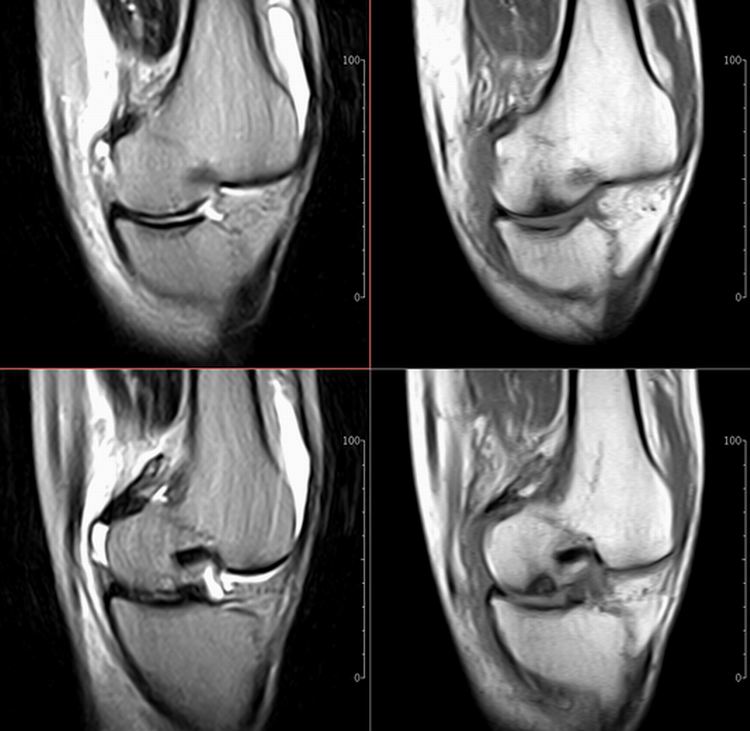

标题: MRI1910:M 687Y。近日因外伤疼痛,而就诊。

m 687y。近日因外伤疼痛,而就诊。有外侧副韧带损伤吗??因片子较差各位请包涵。

这算什么位置呢?矢状位?冠状位?

关节退行性变伴股骨外髁关节面下囊肿,不除外剥脱性骨软骨炎.关节积液,髌骨软化症

体位不标准。关节退变伴关节积液。

1)膝关节骨质退行性改变。

2)由于体位的关系不能确定有外侧副韧带的损伤。

关节退变伴关节积液,外侧副韧带的损伤

关节积液,外侧副韧带的损伤